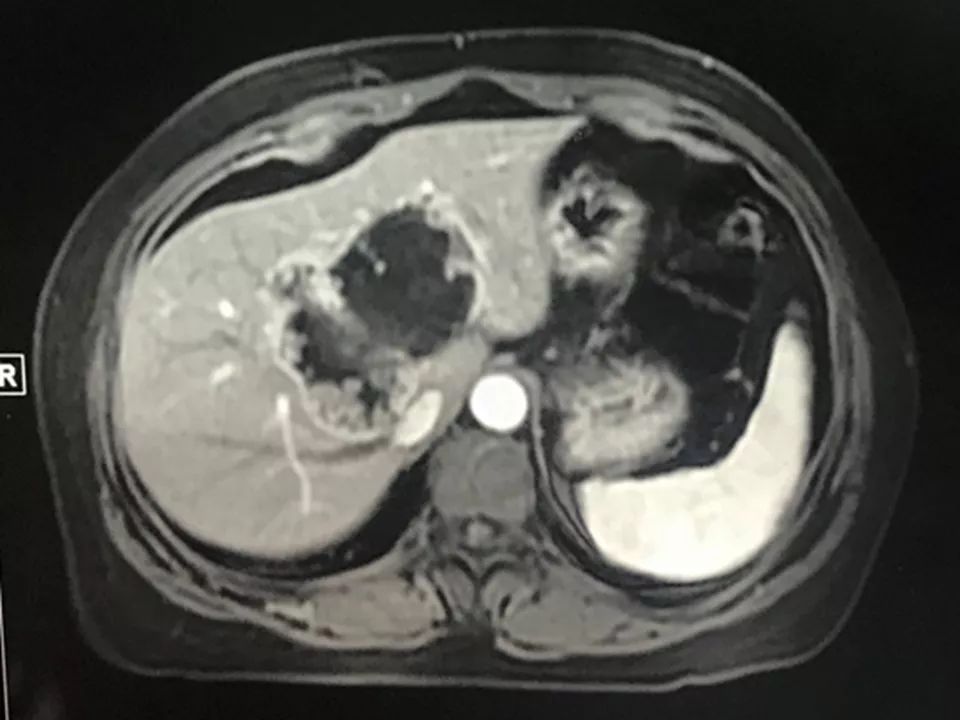

MRI表现:

肝内单发占位灶,累及肝左右叶及尾叶。T1WI示病灶以低信号为主,边缘多枚等信号结节,正反相位未见明显脂肪成份;T2WI示病灶以粘液成份为主呈高信号,边缘多枚稍高信号结节(相对肝实质),DWI呈不均匀等高信号,ADC图以高信号为主。动脉期病灶边缘均匀强化,壁结节显著强化,门脉期边缘仍持续强化,边缘光滑,壁结节呈相对等低信号。MRCP示胆管扩张,病灶与胆管相通。